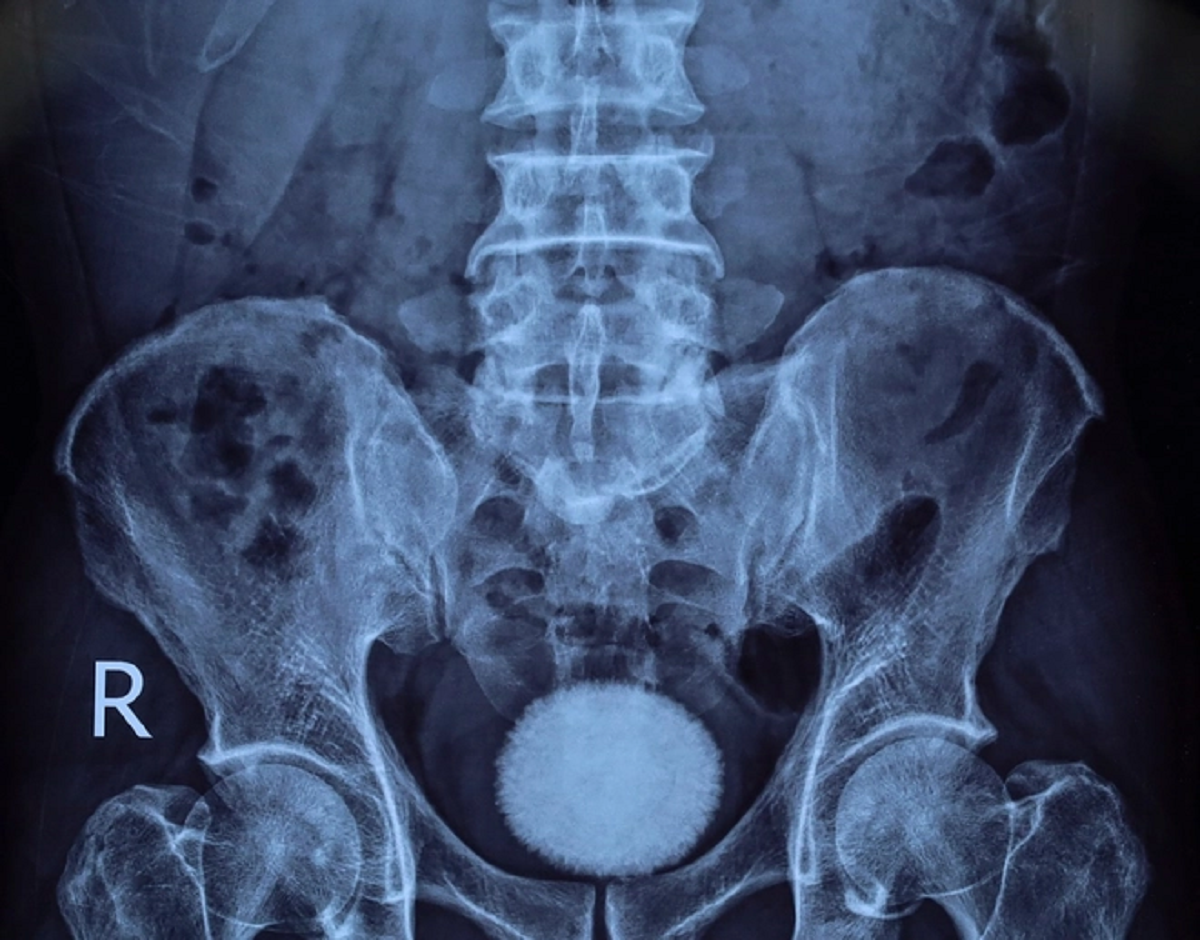

Khai thác tiền sử bệnh trước đó, bệnh nhân đến khám trong tình trạng tiểu buốt, tiểu khó kéo dài, kèm đau vùng hạ vị. Qua thăm khám lâm sàng, siêu âm và chụp X-quang, các bác sĩ phát hiện trong bàng quang có viên sỏi kích thước khoảng 60x40 mm.

Người đàn ông 50 tuổi đau hạ vị kéo dài, bác sĩ sốc khi gắp ra thứ "đáng sợ" bằng quả trứng ngỗng- Ảnh 1.

Nhận định đây là viên sỏi lớn, nguy cơ gây tắc nghẽn và nhiễm trùng đường tiết niệu, ê kíp bác sĩ đã chỉ định phẫu thuật mở lấy sỏi bàng quang.

Trong quá trình phẫu thuật, các bác sĩ rạch da đường giữa trên xương mu, tiếp cận bàng quang và lấy ra một viên sỏi lớn, kích thước tương đương quả trứng ngỗng. Sau khi lấy sỏi, bàng quang được bơm rửa sạch và khâu phục hồi theo đúng quy trình chuyên môn. Ca mổ diễn ra thuận lợi. Hiện bệnh nhân tỉnh táo, sức khỏe ổn định và đang được theo dõi, chăm sóc hậu phẫu.